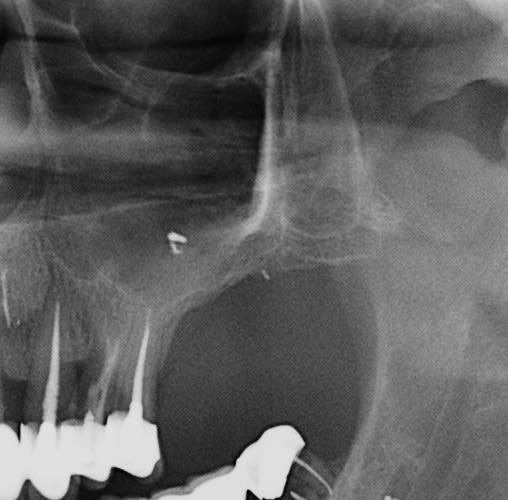

je n'ai pas le scan ici mais si tu regardes secteur 2 du cas présenté plus haut, je ne crois pas avoir beaucoup d'os ... et néanmoins tout a été fait en Summers, (sans doute après ostéotension, ce qui permet de stimuler l'os et de savoir sa qualité)

c'est donc petit a petit que j'ai adapté les techniques, dans le cas en photo, je fais plusieurs soulevé en lieu et place des futurs implants, et je place mon biomat (en principe si 4mm je ne mets souvent que des éponges et les implants en toile de tente), ensuite soit je laisse "murir" 4 mois soit je place les implants de suite...